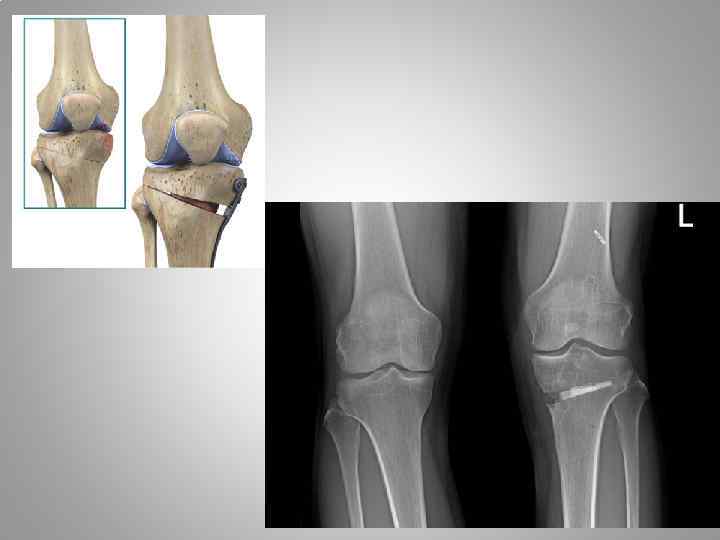

Рентгенография • Первая степень - легкая. При вальгусной деформации механическая ось проходит через центральную часть латерального мыщелка бедренной и центр наружной половины мыщелка большеберцовой кости (отклонение голени кнаружи на 10— 15°). При варусной деформации ось проходит через центральную часть медиального мышелка бедренной и внутреннюю половину мыщелка большеберцовой костей (отклонение голени кнутри на 5 -10°). • Вторая степень - средняя. При вальгусной деформации ось проходит через наружную часть латерального мыщелка бедренной кости, касается латерального края наружного мыщелка большеберцовой кости (отклонение голени кнаружи на 15 -20°). При варусной деформации ось проходит через внутреннюю часть медиального мыщелка бедренной кости и касается медиального края внутреннего мыщелка большеберцовой кости (отклонение голени кнутри на 1015°). • Третья степень - тяжелая. Механическая ось проходит вне коленного сустава, латерально при вальгусной (отклонение голени кнаружи более 20°) и медленно при варусной деформации (отклонение голени кнутри более 15°).